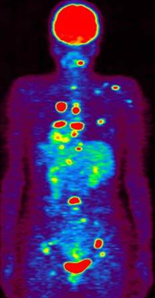

131I-MIBGは、神経堤(neural crest)が発生母地となる神経内分泌腫瘍である褐色細胞腫、傍神経節腫、神経芽細胞腫などに集積するため、このことを利用して、131Iの放出するβ線を用いて癌細胞の内部より選択的に照射を行うRI内照射治療が可能です。褐色細胞腫の約10%は稀ではありますが悪性化することがあり、全身に転移します。この様な症例には、現在なかなか有効な治療法がありませんが、131I-MIBG治療の適応になることがあります。

群馬大学附属病院では、2004年より当院IRBの承認を受けて、年間約10-15症例の悪性褐色細胞腫・傍神経節腫を対象として本治療を行なっています。患者さんは東北、首都圏を中心とした関東全域など広く東日本全域より来院されます。予め、担当医より紹介状の送付を頂き、適応に関して評価を行い、その後患者様の外来受診、検査入院(約5日間)、治療入院(約10日間)という流れで診療が進行します。131I-MIBGは、本邦では未承認薬であるため、ポーランドより個人輸入しています。

結果の一部は論文として発表されています。